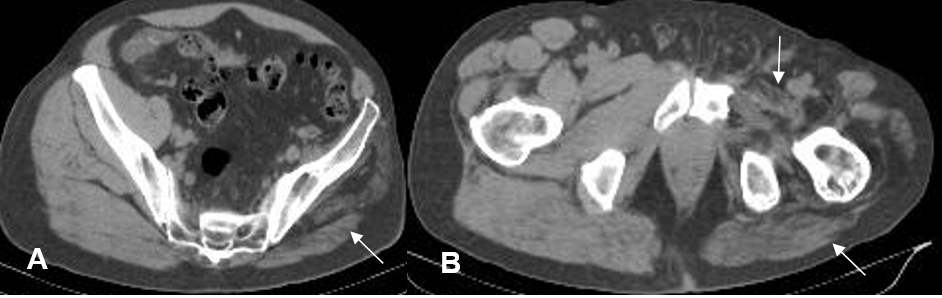

A y B: TAC axial. Pérdida de volumen en los músculos de la región glutea, aductores y rotadores de la cadera, por atrofia muscular.